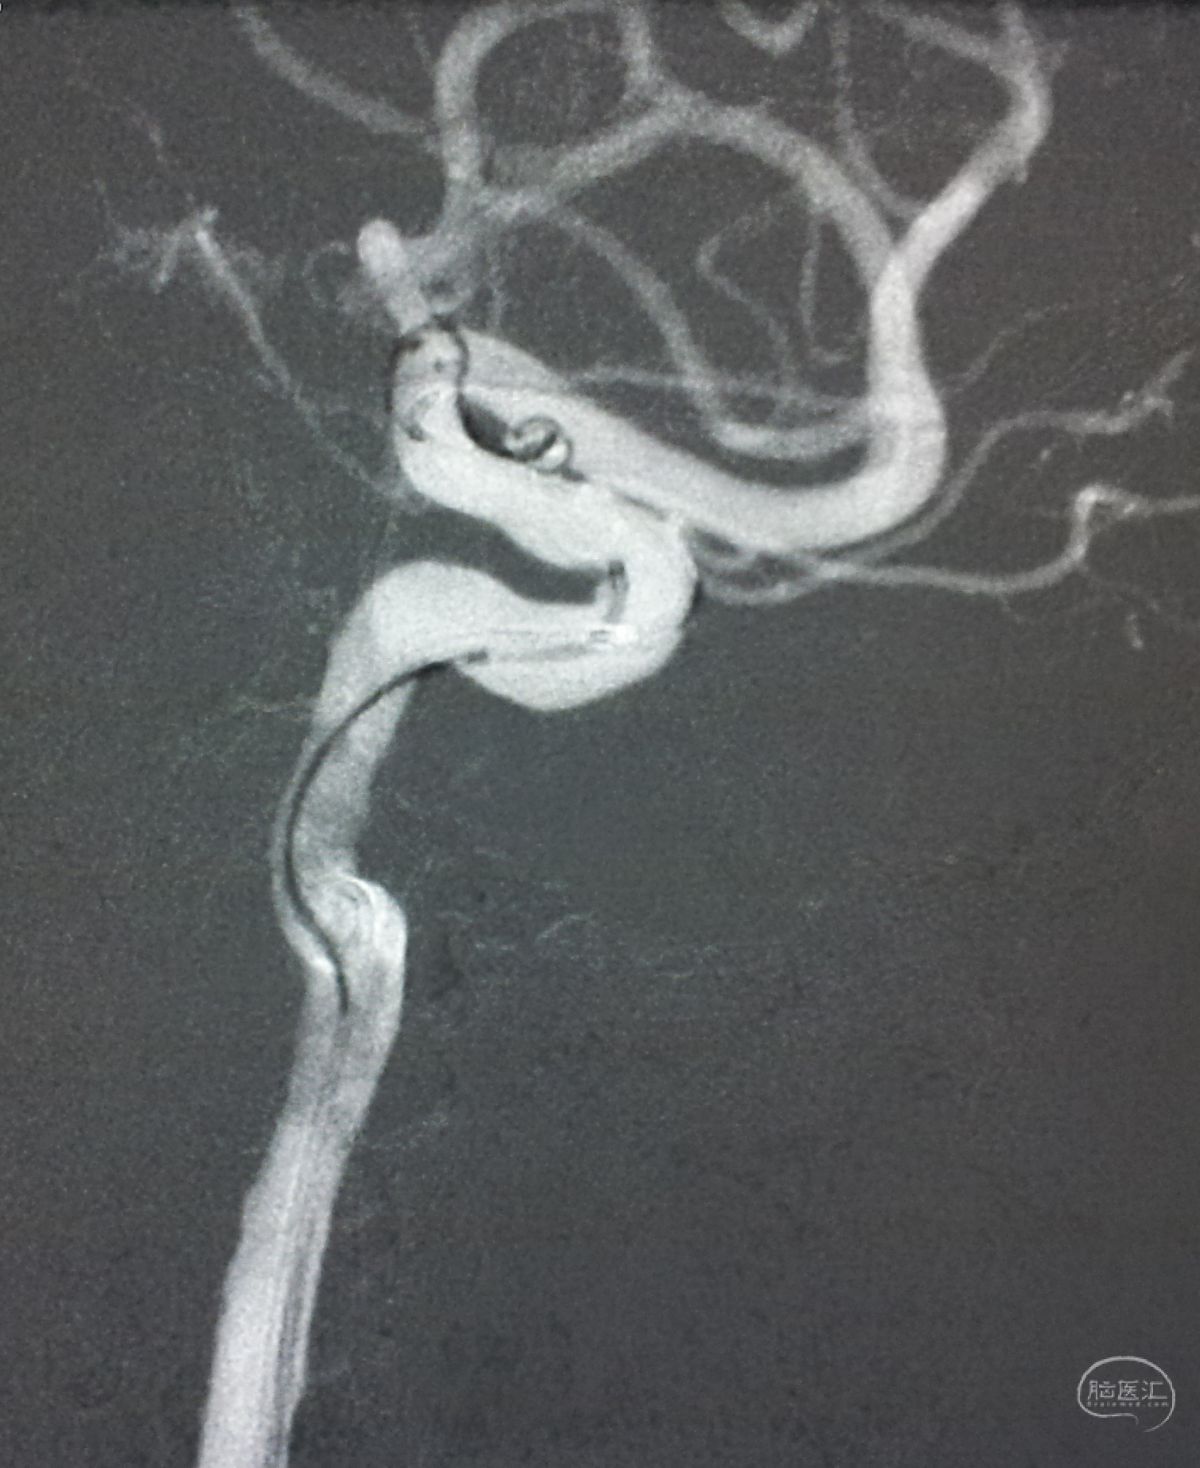

解脱第一枚Solitaire 4×20支架后,套叠置入第二枚Solitaire 4×20支架,置入两枚支架的原因是考虑该瘤是夹层动脉瘤,多支架能够强化血流导向作用,有利于夹层愈合。

术后右椎动脉工作位造影,

以及正位造影显示动脉瘤完全栓塞,载瘤动脉畅通。